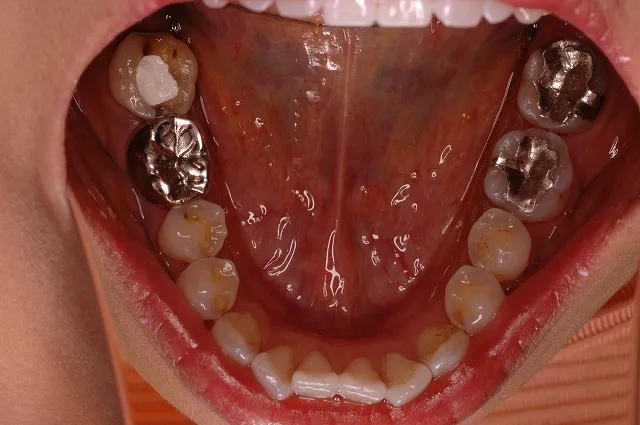

症例4

右下456:セラミックメタルボンドブリッジ

左下4:セラミックメタルボンドクラウン

左下567:インプラント+セラミックメタルボンドクラウン